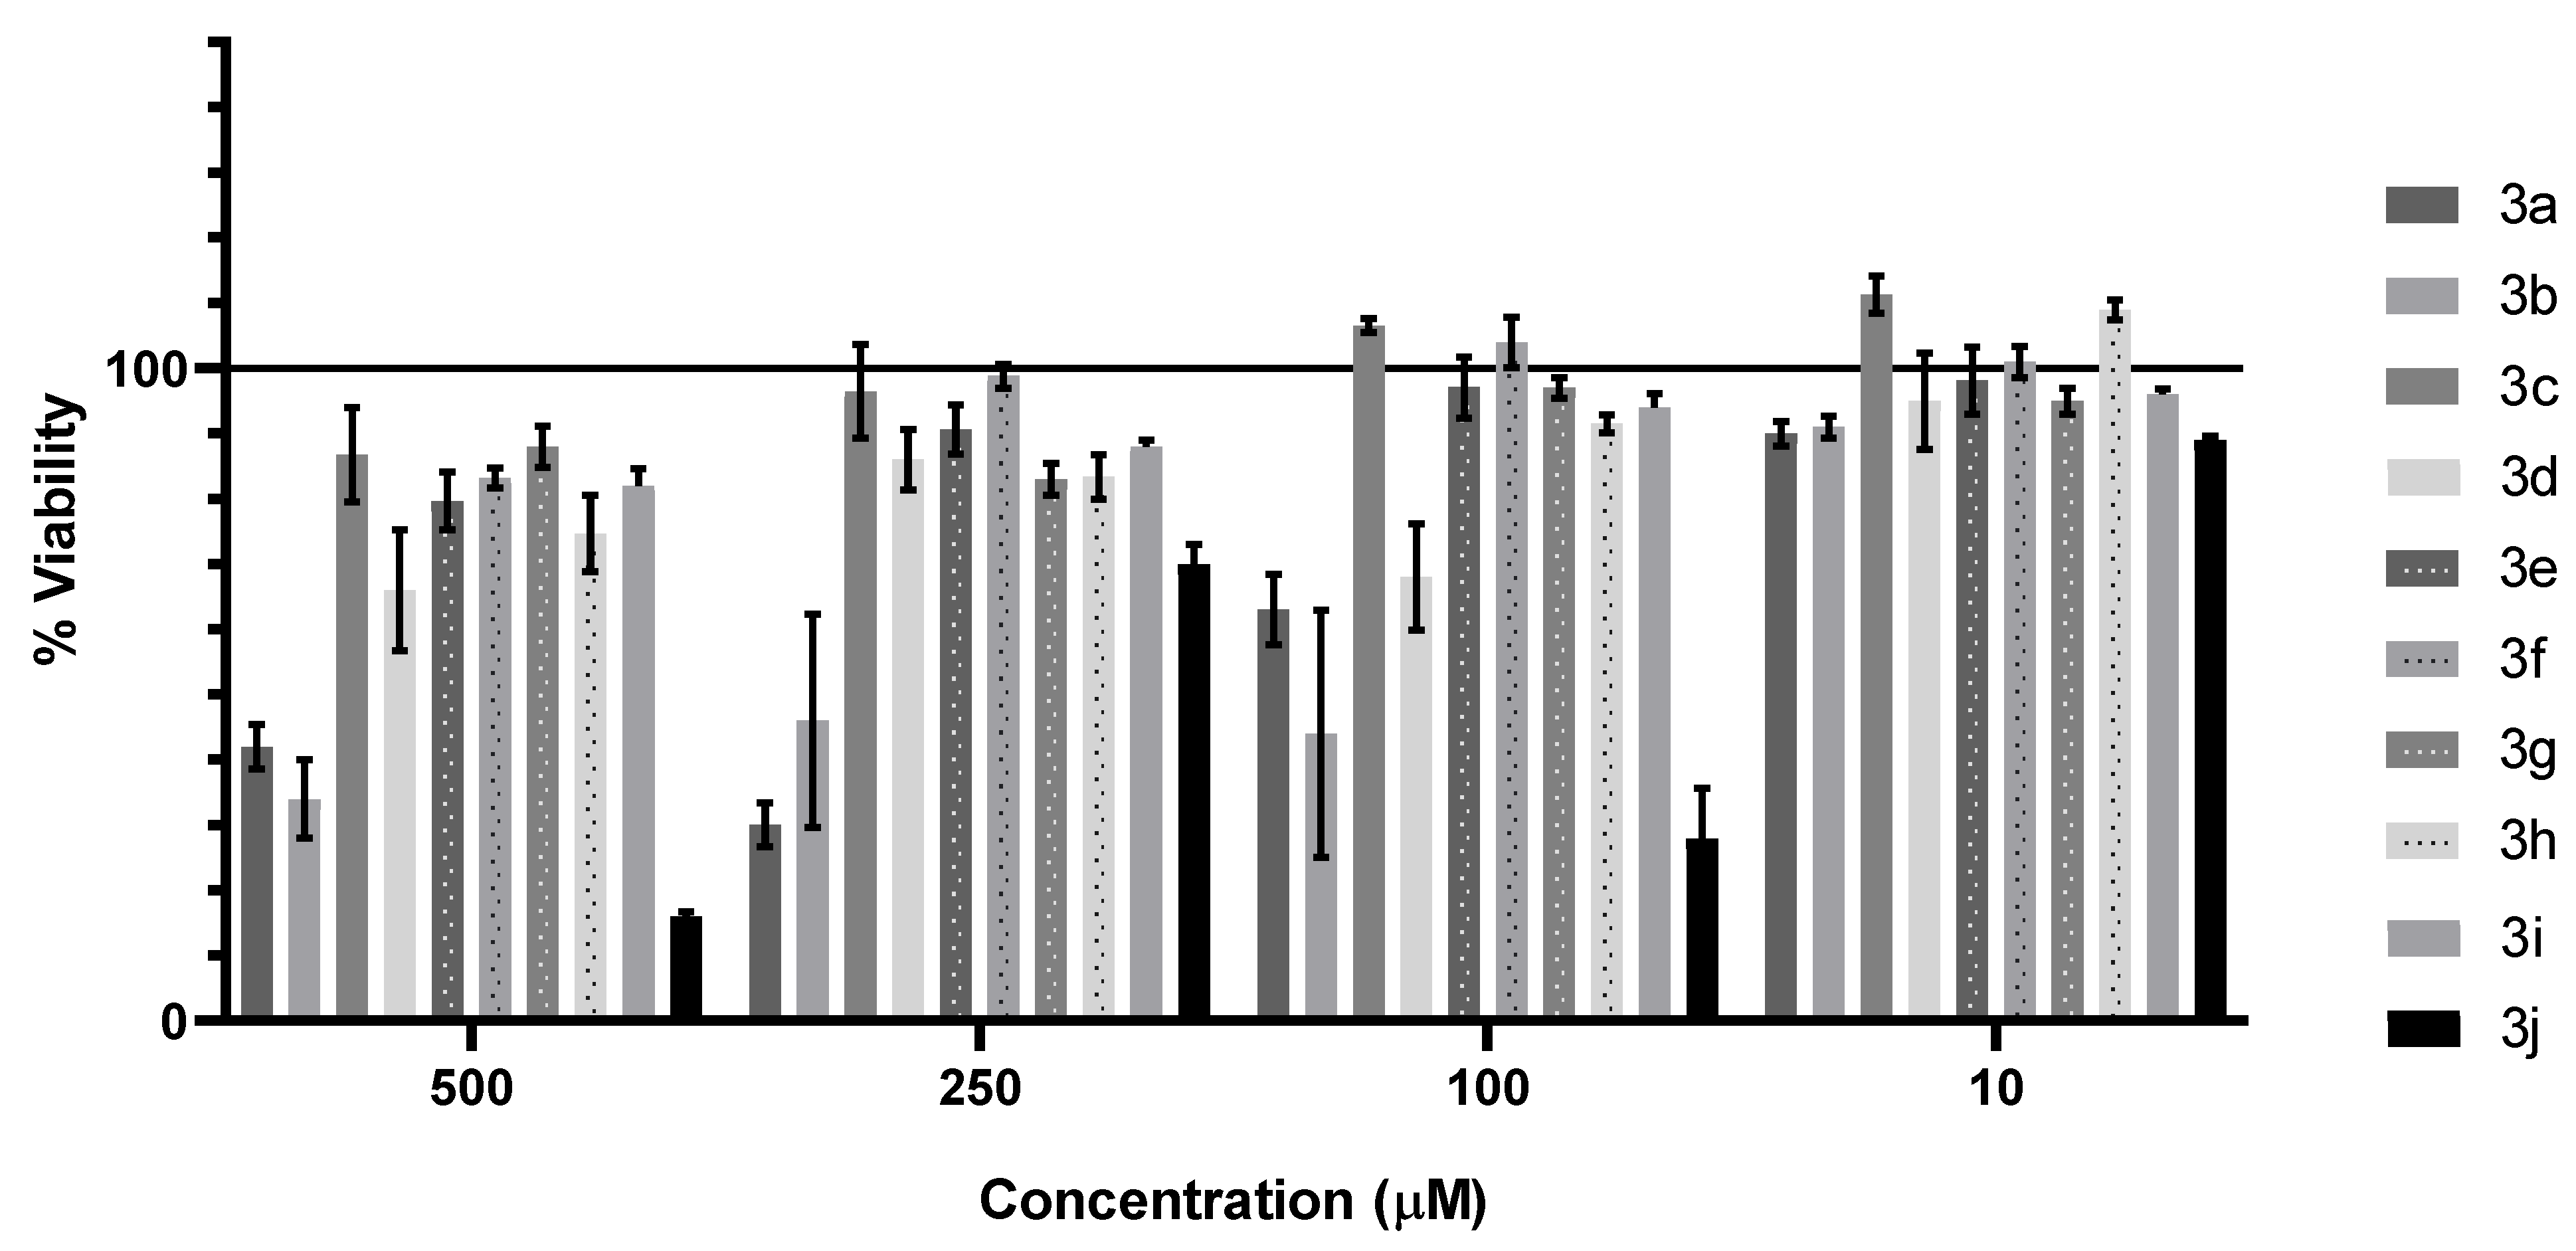

3.3.1. Cytotoxic and Antiproliferative Effect

| HeLa | HepaRG | Caco-2 | AGS | A172 | |

|---|---|---|---|---|---|

| 3a | >250 µM | 200.8 µM | >250 µM | 209.2 µM | >250 µM |

| 3c | >250 µM | >250 µM | >250 µM | >250 µM | >250 µM |

| 3d | >250 µM | >250 µM | >250 µM | >250 µM | >250 µM |

| 3e | >250 µM | >250 µM | >250 µM | >250 µM | >250 µM |

| 3f | >250 µM | >250 µM | >250 µM | >250 µM | >250 µM |

| 3g | 209.4 µM | 183.3 µM | >250 µM | >250 µM | 146.7 µM |

| 3h | >250 µM | 132.3 µM | >250 µM | >250 µM | >250 µM |

| 3i | >250 µM | >250 µM | >250 µM | >250 µM | >250 µM |

| Staurosporine | 1 µM | 1 µM | 1 µM | 1 µM | 1 µM |